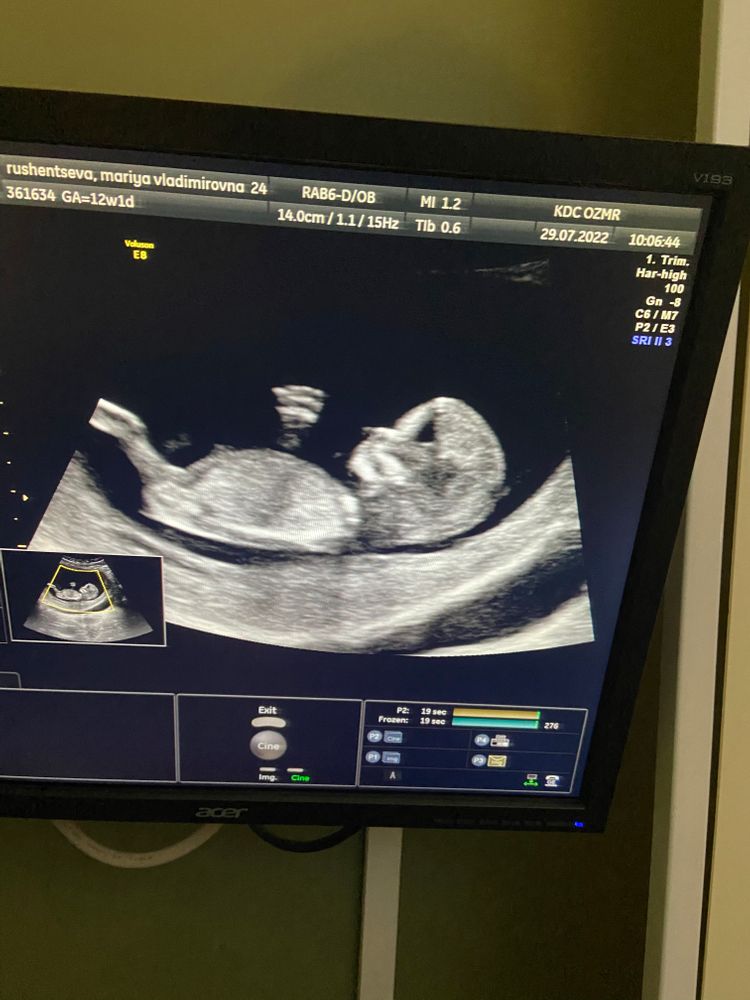

Просто хочу поделиться фото узи и хорошим отзывом о Флотской!

Тоже проходила на флотской два скрининга) всё очень понравилось!!! В восторге от узиста Мостовой Натальи Владимировны!!! С полом не ошиблась в 13 недель)